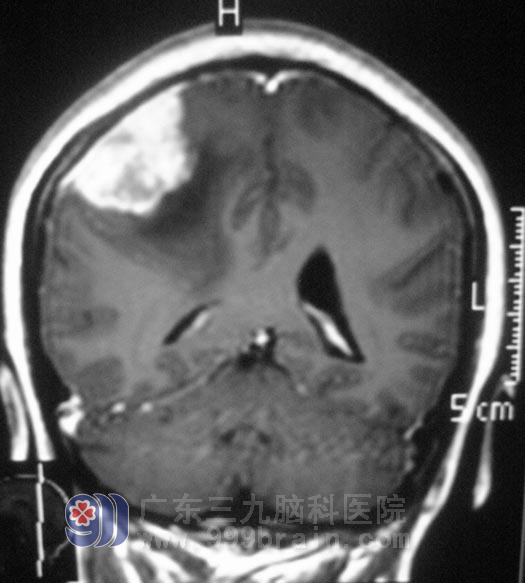

在广东三九脑科医院进一步检查,头颅MR检查提示右侧额顶部占位性病变,大小约4.3cm×4.2cm×2.2cm,考虑脑膜瘤。综合神经外科 鲁明主任为王女士在全麻下行右侧额顶部脑膜瘤切除术,术中切开硬脑膜后,显微镜下见肿瘤与硬膜粘连紧密,位于额顶部,肿瘤部分呈灰白色,质地、血运一般,与脑组织边界较清,予肿瘤全切。术后王女士没有出现肢体偏瘫等不良并发症。术后经病理证实为:合体型脑膜瘤。

▲手术前